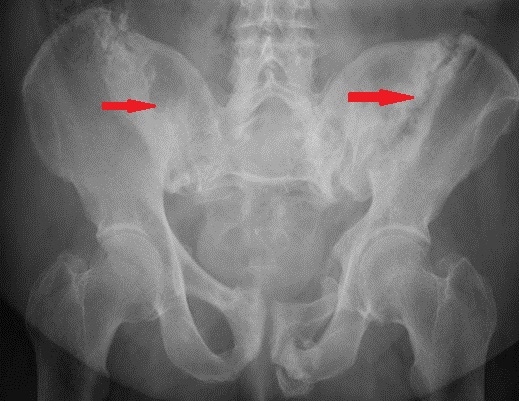

Un bărbat din Micro 17, locatar al blocului H, a reuşit, vineri spre sâmbătă, să ajungă la Spitalul de Urgenţe, cu bazinul fracturat, după ce a încercat să modifice ţeava unui aparat de aer condiţionat. Potrivit coordonatorului UPU – SMURD Galaţi, Angel Trifan, bărbatul a căzut de la etajul 1, iar la Urgenţe s-a constatat că bărbatul consumase alcool. "S-a căţărat să modifice ţeava pentru că era deranjat de zgomotul făcut de apa care se scurgea din aparatul de aer condiţionat şi care cădea pe casa scării, nelăsându-l să doarmă", ne-a spus coordonatorul UPU - SMURD.